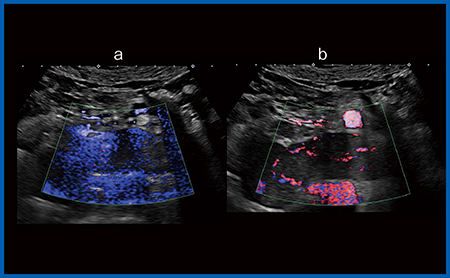

SMI(Superb Micro-vascular Imaging)をより高感度でノイズレスにした血管表示法である“iSMI”が新たに開発された。SMIは,非造影で高いSN比で低流速の血管描出を可能にしたが,例えば,視野角を広げた時にクラッタノイズが発生する,高感度とはいえSN比の限界で観察できない血流があるなどの悩みがあった。iSMIではこれらの課題を改善し,高感度でより精細な血流の表示が可能になった。図7は,腎がんに伴う左腎静脈腫瘤塞栓だが,大動脈直上のため拍動によるクラッタでOriginal SMI(a)では観察が難しいが,iSMI(b)ではクラッタの影響を受ける時間が短くなり,腫瘍塞栓であることが診断できる。さらに,感度が向上した新しい7MHzプローブ(PLI-705BX)を使うことで,胃のGISTの転移性肝腫瘍ではiSMIで造影剤を使用せずに質的診断に迫る画像が得られている(図8)。

図7 腎がんに伴う左腎静脈腫瘤塞栓の描出

a:Original SMI b:iSMI

図8 転移性肝腫瘍(胃GIST)